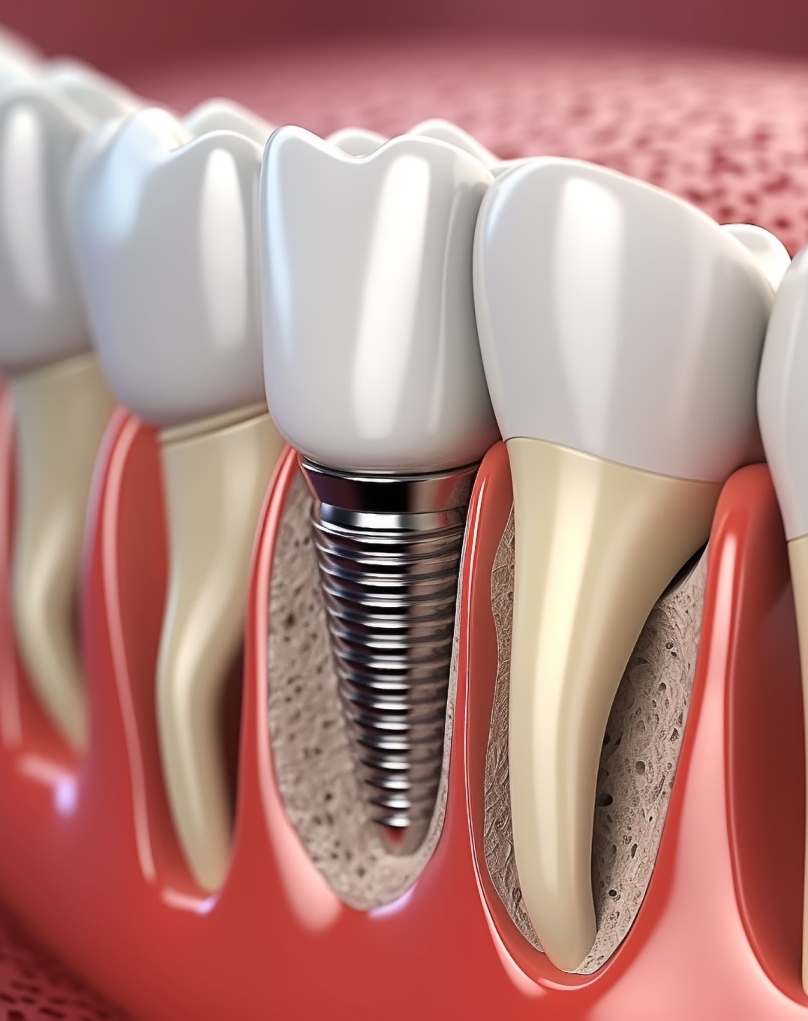

Implantes Dentários

Os implantes dentários são a solução mais eficaz para substituir dentes perdidos. Consistem em pequenas estruturas de titânio colocadas no osso, que funcionam como raízes artificiais para suportar coroas ou próteses fixas. Garantem estabilidade, conforto e uma aparência natural, devolvendo ao paciente a função mastigatória e a confiança no sorriso.